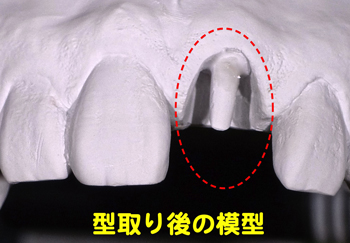

ぶらぶらしていた前歯を取りました。歯茎のかなり奥に折れた残りの歯が確認できます。ここに差し歯を装着する事は、相当難しい作業の連続が予測されます。

ぶらぶらしていた前歯を取りました。歯茎のかなり奥に折れた残りの歯が確認できます。ここに差し歯を装着する事は、相当難しい作業の連続が予測されます。

お口の状態を正確に石膏模型で再現しました。この後、セレックにてオールセラミックの被せ物を製作することに。ここまで治療開始から8日。

お口の状態を正確に石膏模型で再現しました。この後、セレックにてオールセラミックの被せ物を製作することに。ここまで治療開始から8日。